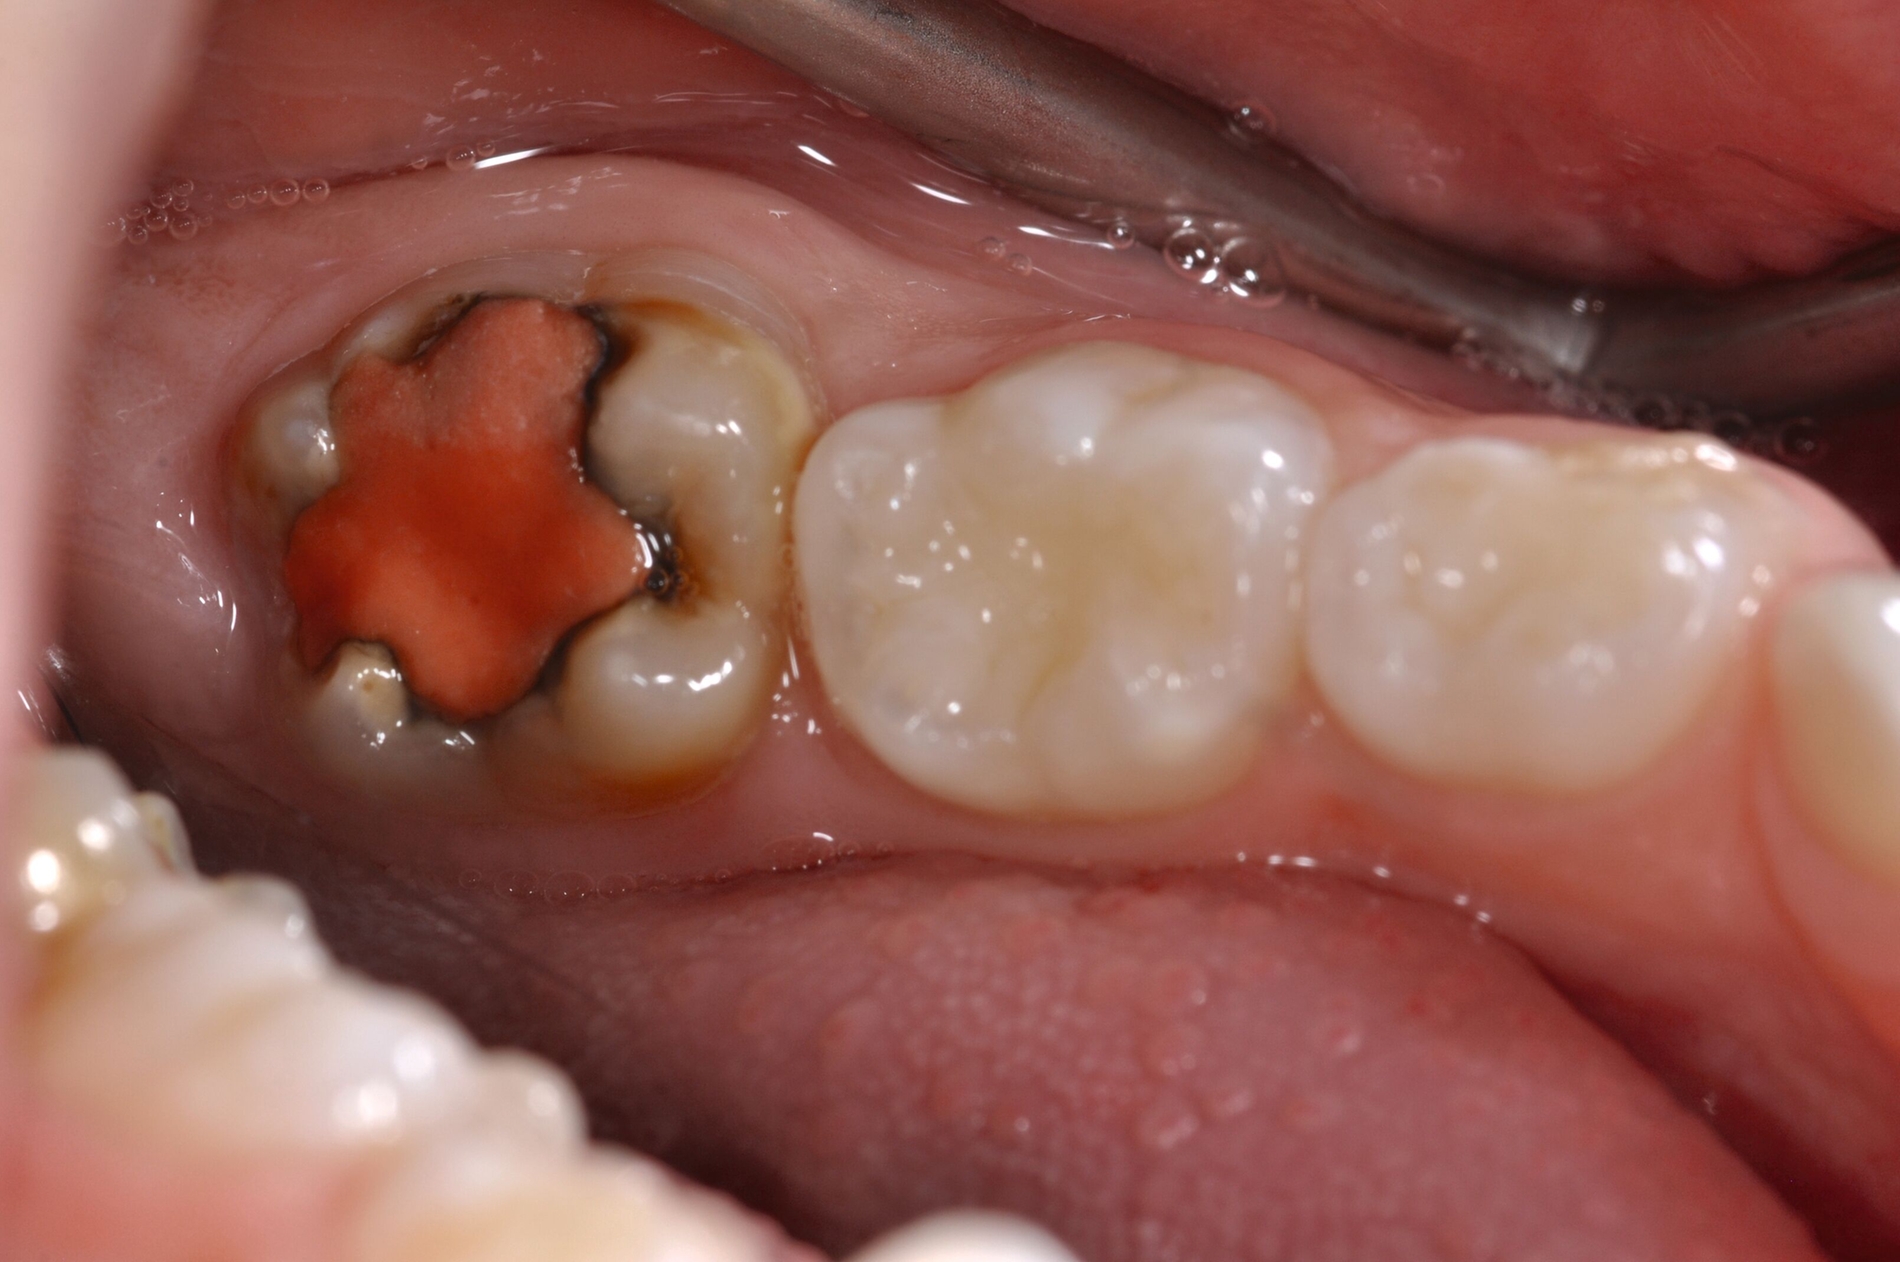

Diese Klassifikation dient als Grundlage für die Therapieempfehlungen. Deutlich wird, dass aufgrund der Symptomatik die Therapie der Zähne höchst unterschiedlich ausfällt. Dass etwa eine Opazität ohne Überempfindlichkeit (Index 1, Abbildung 1) ein anderes therapeutisches Vorgehen erfordert als ein Zahn mit nahezu komplettem Einbruch der Zahnoberfläche und mit Hypersensitivität (Index 4, Abbildung 2), ist offensichtlich.

Die Therapie C hat das Ziel, MIH-Zähne vorübergehend zu versorgen, bis der vollständige Durchbruch der Zähne eine adhäsive Restauration ermöglicht, um die hypersensiblen Zähne zu desensibilisieren oder/und die Mitarbeit für die weitere Behandlung aufzubauen. Vor dem Hintergrund des erhöhten Kariesrisikos dieser Zähne (Abbildung 2) muss durch die Maßnahmen eine Kariesprogression vermieden werden.

Als mögliche Maßnahme steht eine Abdeckung der Defekte mittels konventioneller Glasionomerzemente (GIZ) zur Verfügung. Vorteil der Materialien ist die schnelle und einfache Applikation der Zemente. Bei MIH-Molaren werden diese in der Regel mittels der sogenannten ART-Technik (Atraumatic Restorative Treatment) eingesetzt [Grossi et al., 2018]. Dabei wird lediglich mit einem Handinstrument die Zahnoberfläche gereinigt und gegebenenfalls Karies exkaviert. Anschließend wird die Kavität unter relativer Trockenlegung mit dem GIZ aufgefüllt.

Der Vorteil der Methode ist, dass die betroffenen Zähne auch ohne Lokalanästhesie und Präparation versorgt werden können. Die temporäre Versorgung ermöglicht es, die Patienten an die zahnärztliche Behandlung zu gewöhnen. Häufig führt diese temporäre Versorgung auch zu einer Reduktion der Hypersensitivität der MIH-Zähne. Nachteil der GIZ-Versorgung ist das Risiko einer Füllungsfraktur oder eines vollständigen Verlusts der Füllung (Abbildung 4). Aktuelle Erhebungen bestätigen eine Erfolgsrate von über 80 Prozent nach einem bis zwei Jahren [Durmus et al., 2021; Mahfouz et al., 2025].

Der Behandlungsfall (Abbildung 4d) veranschaulicht die Schwächen des Verfahrens. Wird das Angebot der regelmäßigen Kontrollen nicht wahrgenommen, so droht bei Verlust der Füllung die Kariesprogression. In dem vorliegenden Fall konnte jedoch eine endodontische Maßnahme vermieden und durch die selektive Kariesentfernung die Zahnhartsubstanz weitestgehend erhalten werden.